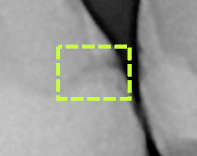

Results of the restoration imperfections analysis - Dashed yellow squares/rectangles appear on the image where possible areas of decay and open margins under restorations were detected.